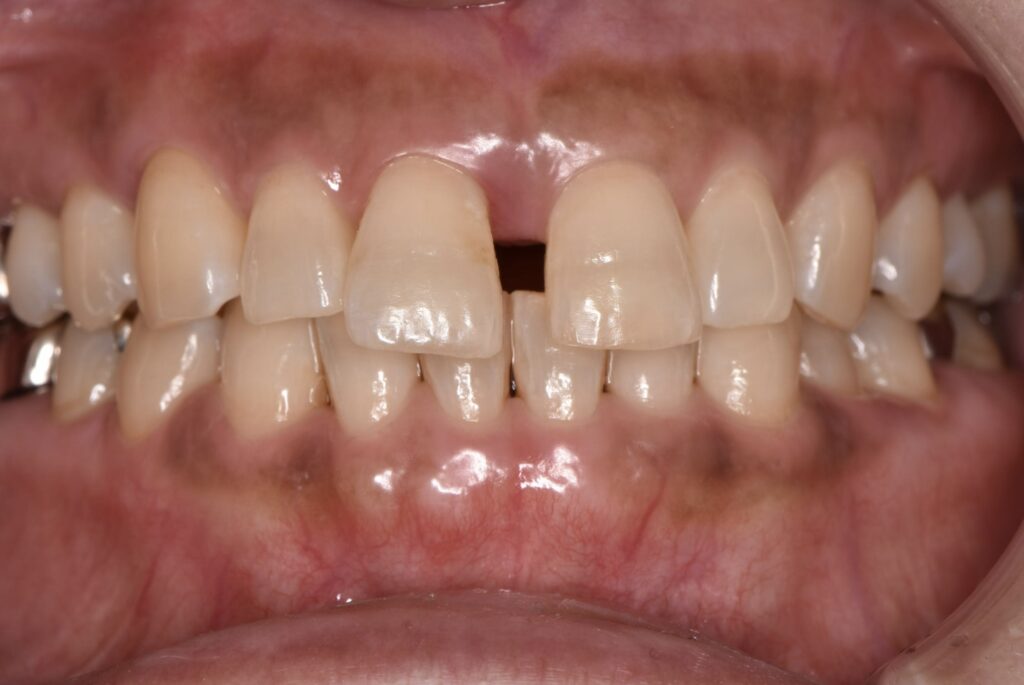

【マウスピース矯正】

矯正前(正面・側貌)

矯正後(正面・側貌)

主訴すきっ歯

初診年齢38歳

治療内容、装置アライナー

抜歯、非抜歯非抜歯

治療期間8ヶ月

費用473,000円

(相談料、検査料、診断料、動的治療費、保定期間料を含む)

治療のリスク、副作用歯の移動に伴う痛み

上下顎前歯部の歯根吸収

ブラッシング不良によるむし歯、歯周炎